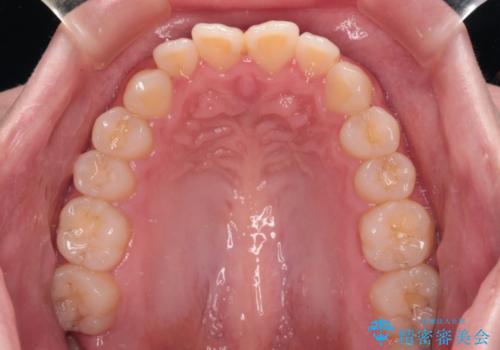

舌の突出癖により上下前歯は接触できず、更には前方に押し出されて出っ歯になっている状態でした。

上下左右の第一小臼歯4本を抜歯し、ワイヤー装置での抜歯矯正を行っていくのですが、原因である舌の突出癖を改善しないことには治療がうまく進められないため、舌のトレーニングを徹底するよう指導していくこととしました。

当初は舌のトレーニングをしっかりと行ってくださったおかげで、短い期間で治療を終えることができました。